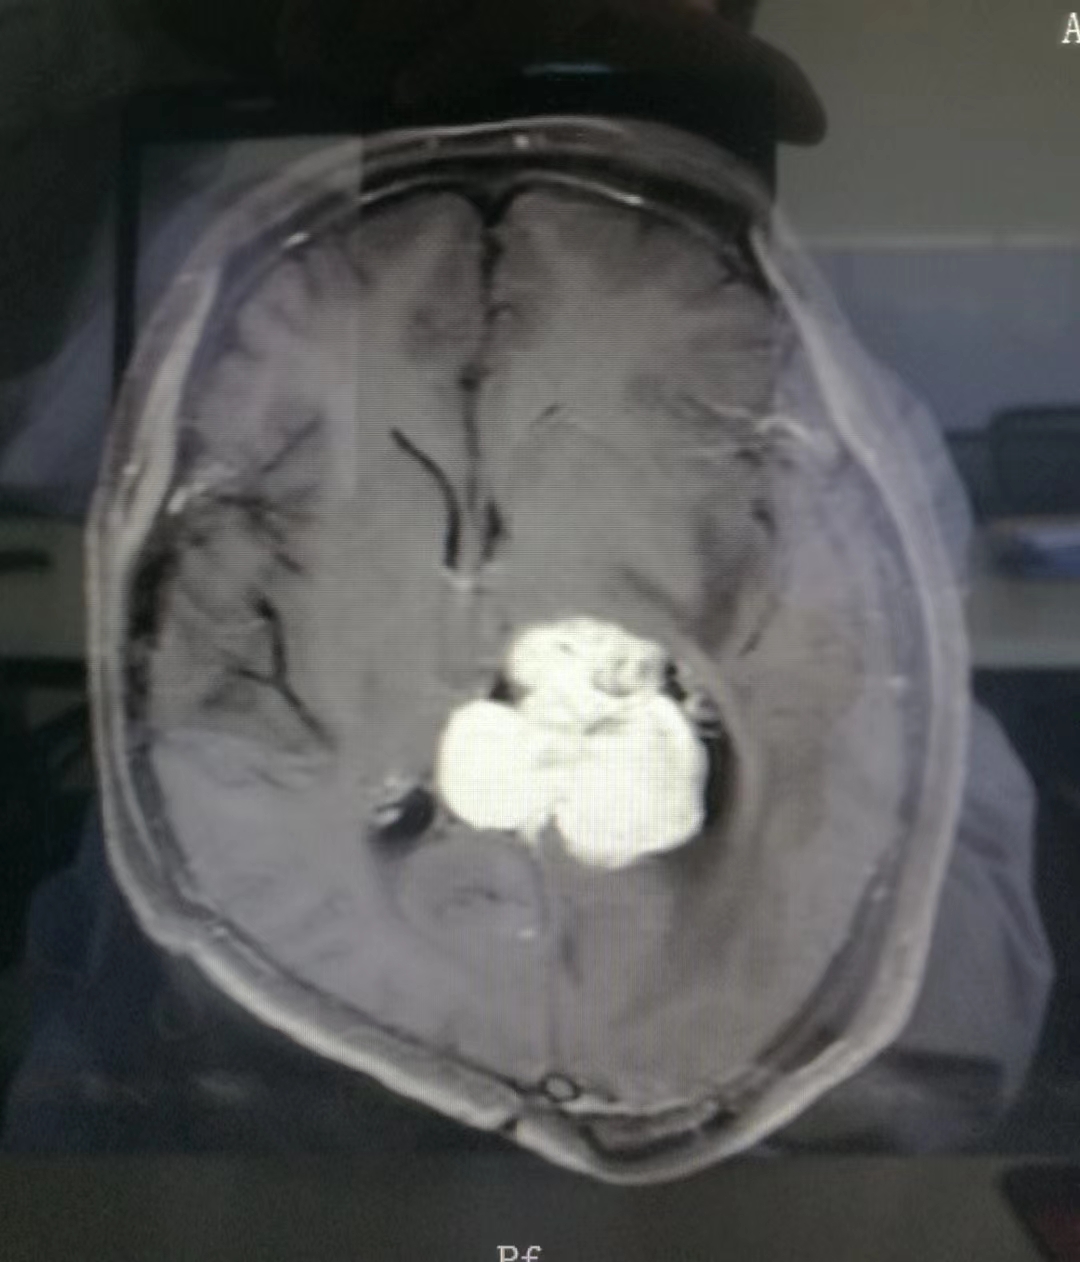

术前MRI